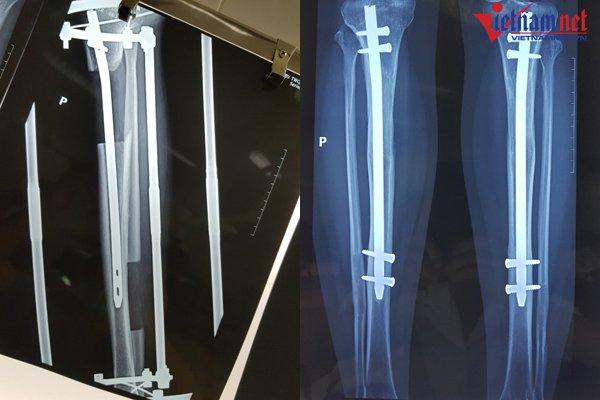

Một chiếc đinh dài được đặt trong lòng ống tủy (trái) và bác sĩ sẽ bắt chốt 2 đầu đinh lại sau khi đạt chiều cao mong muốn

Khi đạt đến chiều cao mong muốn, bác sĩ sẽ bắt chốt 2 đinh lại với nhau và tháo bỏ khung ngoài. Bệnh nhân sẽ được bó bột, sau đó bắt đầu tập đi dưới sự trợ giúp của khung hoặc nạng.